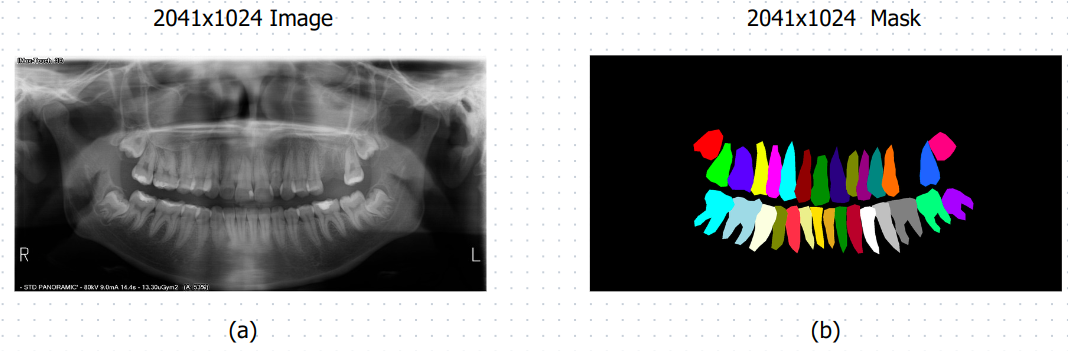

The dataset utilized in this study consists of 598 panoramic X-ray images and their corresponding segmentation masks. Each image has a resolution of 2041x1024 pixels, ensuring a high level of detail for precise tooth segmentation. The dataset includes a total of 33 classes, with individual labels assigned to each tooth and an additional label for the background. This multiclass labeling approach facilitates a more granular segmentation, addressing challenges such as overlapping and indistinct boundaries between adjacent teeth.

The segmentation masks are meticulously annotated to ensure accurate representation of each tooth, making the dataset suitable for both training and evaluation in multiclass segmentation tasks. The class distribution is balanced across the dataset, providing sufficient samples for all tooth classes. A summary of the dataset is presented in the table below:

Figure 1:

Example images and masks are illustrated in Figure 1.